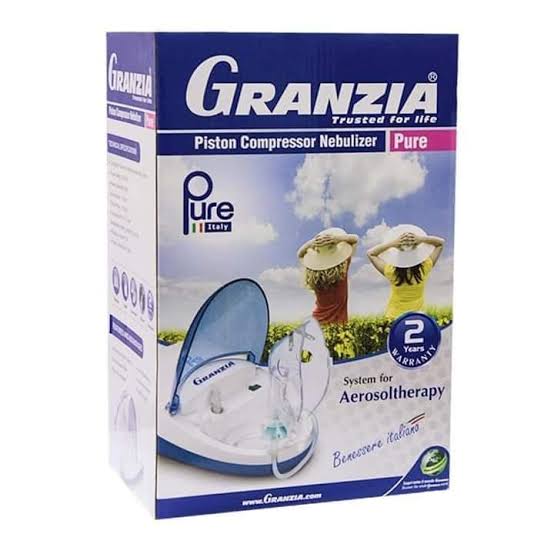

27% خصم

جهاز جلسات تنفس جرانزيا بيور

1,100 جنيه

1,500 جنيه